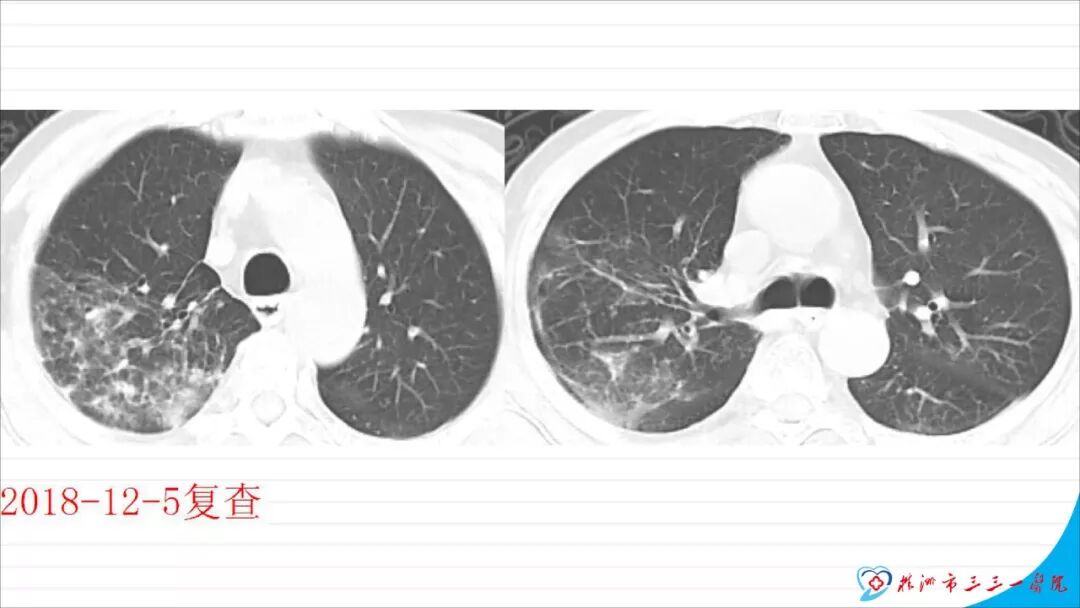

今天为大家分享的是《颅脑创伤-神经重症病例周刊》第113期,由株洲市三三一医院神经外科毛德龙医师带来的:老年病人慢性硬膜下血肿自然演变一例 ,天津医科大学总医院神经外科副主任兼NICU主任、“神外资讯中国颅脑创伤-神经重症专家组”委员江荣才教授对病例作出了精彩点评,欢迎观看、阅读。

本文以“慢性硬膜下血肿自然演变一例”为题,恰当!因为此例患者系从急性硬膜下血肿自然演变而来。只是长期口服他汀没有起到预防作用。本例患者与其说是阿托伐他汀治疗慢性硬膜下血肿无效,还不如说是阿托伐他汀不能阻止急性硬膜下血肿向慢性硬膜下血肿演变的过程,当然,后续急性血肿变成慢性后,阿托伐他汀似乎也没有发挥治疗作用。需要指出的是,单药阿托伐他汀治疗急性硬膜下血肿并无成功病例报道,但是,本例报道还告诉我们,它还不能阻止急性硬膜下血肿向慢性血肿演变,值得关注。 谈到阿托伐他汀治疗慢性硬膜下血肿,我们是始创者。为此,看到作者似乎有点抱怨的情绪,我得做些解释。我们ATOCH试验,验证的是阿托伐他汀治疗慢性硬膜下血肿比安慰剂能更有效促进血肿吸收,没有发现也没有努力去验证阿托伐他汀治疗慢性硬膜下血肿100%有效,因此发生治疗无效很正常。 保守治疗的始作俑者是英国人,他们1962年就提出地塞米松治疗慢性硬膜下血肿。但是,迄今为止,无论是英国人提出的地塞米松、美国人提出的氨甲环酸或血管紧张素转换酶抑制剂,还是德国人提出的塞來西布,日本人提出的汉药,国内许多单位自行研究提出的血府逐瘀丸,作者单位的“传统”方法红花注射液治疗慢性硬膜下血肿都没有经历严格随机双盲安慰剂对照研究,也从未被大宗病例报道证实过有效。由于未被RCT(随机对照临床试验)证实过,加上一部分慢性硬膜下血肿不必治疗也可以自我吸收(这在我们ATOCH里的安慰剂组中已经观察到,但我们发表论著时没有刻意提出这一点而已),除他汀疗法之外的药物疗法被怀疑是否真具有疗效就顺理成章了。这也是我们的阿托伐他汀治疗慢性硬膜下血肿在保守治疗药物队伍中“一骑绝尘”的理由。后续西南医科大学和香港中文大学还均报道使用阿托伐他汀可以预防慢性硬膜下血肿术后复发。而且,除了有RCT结果支撑其有效性外,安全性明显优于上述各个西药又不像中药或汉药那么含糊,也使得阿托伐他汀成为目前保守治疗慢性硬膜下血肿应用最多的药物。 但毫无疑问,实践中确实屡屡有发现效果不佳的病例。为什么会这样呢?可能有2个理由: 1、确实存在一部分对他汀治疗反应不佳的患者。我们的ATOCH中,阿托伐他汀试验组就有11例患者因无效转去接受手术(对照组则多达23例); 2、ATOCH试验长达8周,有些患者家属和医生都没有耐心等待8周。也就是说,没有等到药物作用显现就转保守治疗为手术治疗。在同样状况下,即使作为发明者,我也不敢“阻扰”患者转手术治疗,因为这意味着风险转嫁。而这种“保守治疗未到时间”(这样提可能不严谨,因为没有规定时间,只有经验时间)就转手术治疗,会增加阿托伐他汀治疗慢性硬膜下血肿的“无效率”。 有鉴于此,我们团队在张建宁教授指导下,从2014年就开始优化阿托伐他汀疗法,本人以此优化的独门方法就治愈了多达200余例各种慢性硬膜下血肿患者。最近,有上海同行私下告诉我,他用类似我的优化方法保守治疗慢性硬膜下血肿多例,还没有失败过。我跟他开玩笑:“那是你治疗的病例还不够多。”实际这不是开玩笑,因为本人有失败经验。目前,我们团队正积极推进ATOCHII试验,就是要证明我们的优化疗法更加有效,期待奉献给世界一个更加好用的治疗慢性硬膜下血肿新方法。 最后需要特别指出的是,慢性硬膜下血肿与急性硬膜下血肿和亚急性硬膜下血肿并非一定有如父如子的“传承”关系。实践中,绝大多数患者都没有急性硬膜下血肿过程,尤其是老年患者第一次查影像学多数就可以确诊慢性硬膜下血肿了,患者之前并没有经历急性硬膜下血肿这种剧烈损伤过程。还有,脑转移癌可以发生类似慢性硬膜下血肿的血肿性病变,先天性蛛网膜囊肿、脑池囊肿术后常见并发症就包括硬膜下血肿。笔者诊疗慢性硬膜下血肿接近300多例,还见过教科书和个案报道没有记载的各种非脑外伤相关慢性硬膜下血肿的病例。相比于脑外伤引起的急性和亚急性硬膜下血肿,慢性硬膜下血肿是处理简单且病情稍显轻微的疾病,但其发生机制却远比急性和亚急性硬膜下血肿更为复杂,值得进一步深入研究。 江荣才 教授 副主任兼NICU主任 天津医科大学总医院神经外科![]()